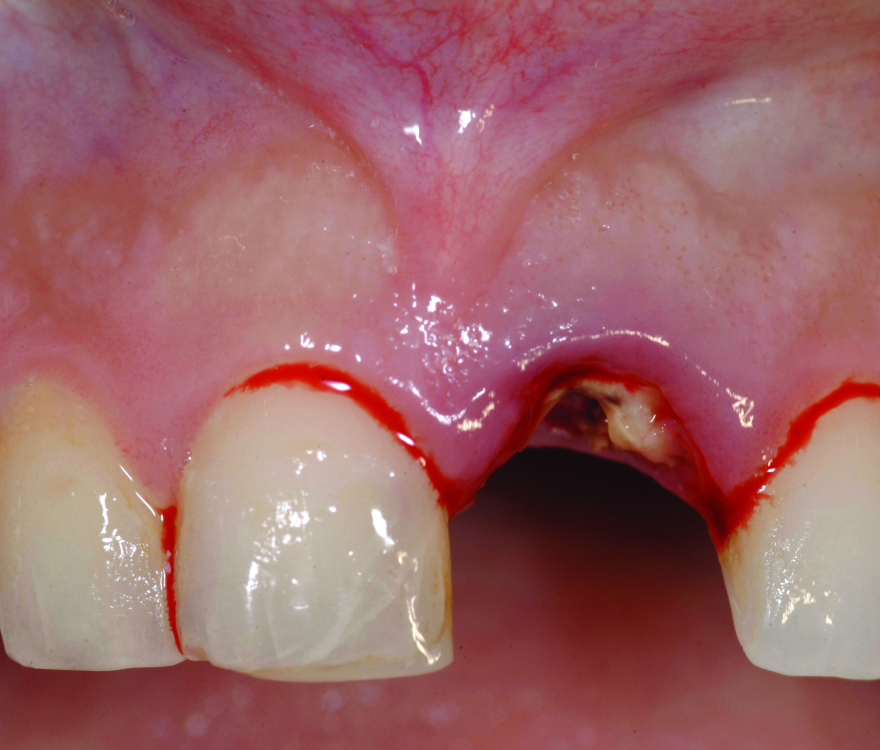

Fig 17. Preoperative view of the fractured No. 9.

Figure 17